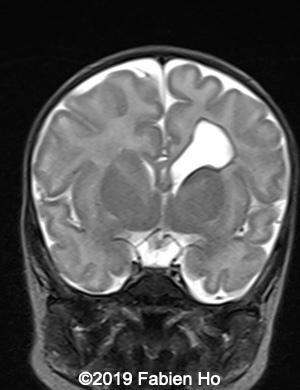

Images 12-16: we performed a second fetal brain MRI at 32 weeks, which showed the same findings as the postnatal neonatal brain MRI as follows:

The evolution of the images is typical of a clastic lesion: after resorption of the ischemic tissue and hematoma, there was now a focal porencephaly with hemosiderin tattooing on its margins. Conversely, persistence of the same MRI findings would have indicated an hypercellular brain tumor, which could have been a differential diagnosis.